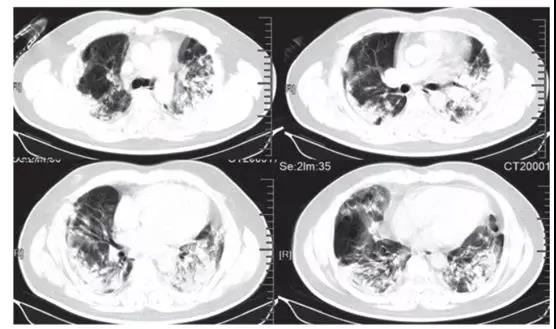

隨后的胸部CT顯示雙側毛玻璃樣混濁,而實變消除(見下圖)。